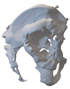

A 3D pelvis reconstruction allowed further processing using the Mimics Innovation Suite (Materialize NV, Leuven, Belgium), which is an engineering software package that enables 3D medical imaging and surgical-related planning. So, the design of the patient-specific aiming device was based on a 3D reconstruction of the patient’s own anatomy. After importing and transforming the two-dimensional Digital Imaging and Communications in Medicine (DICOM) standard file, the radiation absorption range was selected using the windowing method for spatial imaging of the reliable bone structure (Figure 1).

Figure 1.

3D images of the mask that appeared when the CT scans were threshold and the spatial model derived from it. The heads of the implanted screws are displayed in purple.

The default threshold window ranges from 200 to 2000 HU according to the Hounsfield scale, modified to consider the parameterization of the recordings and the specific density of the selected bones.

The selected range is immediately displayed on the screen so that the consequence of the change in the threshold values can be immediately evaluated on the CT slice images in the form of a colored highlight.

The mask obtained in this way contained only the real bone volume relevant to the task, in our case, the pelvis with significant bone defects and the femur on the same side.